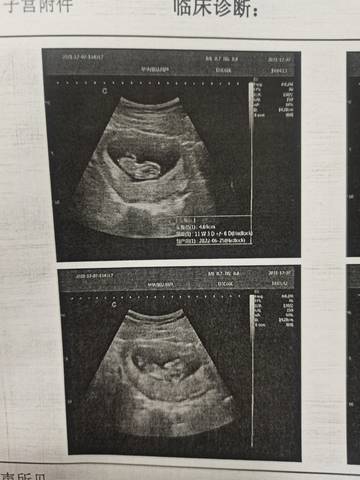

NT一次过了,第一次怀孕。好奇男宝宝还是小棉袄,有明白的能帮忙看看嘛胎心160 NT0.2

journal_insert_pic_1675676350journal_insert_pic_1675676378

你好。我们是判断不了男宝宝跟女宝宝的,孕期定期检查,我觉得宝宝健康就好的。祝心想事成 。

你好,通过这个来判断不太准确,不管是男宝宝还是女宝宝,都是妈妈的小惊喜,祝你心想事成。